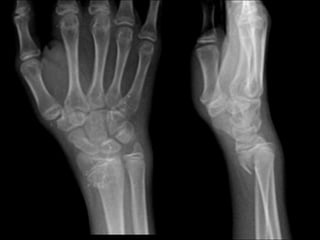

X-ray Right wrist

AP,Lateral

Associated conditions

• DRUJ injuries

• radial styloid fractures

• soft tissue injuries

• scapholunate ligament injury

• lunotriquetral ligament injury